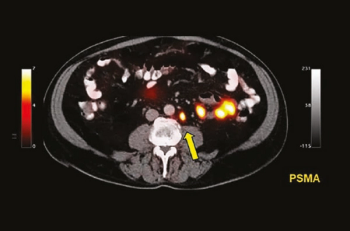

The targeted radioligand therapy 177Lu-PSMA-617 also improved progression-free survival when added to best standard of care (BSC) compared with BSC alone.

Findings support the modality’s use in biochemically recurrent prostate cancer, investigator says.